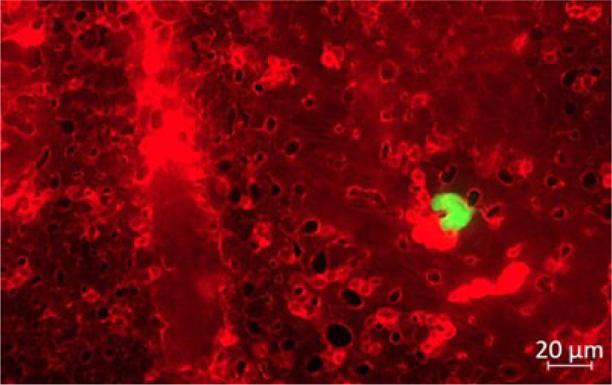

The canine D-17 OSA cell line was cultured and inoculated with decreasing concentrations of PEG-liposomal doxorubicin and conventional doxorubicin in a 3-(4, 5-dimethylthiazol-2-yl)-2, 5-diphenyltetrazolium bromide (MTT) test of cell viability, proliferation and cytotoxicity. Flow cytometry with Annexin V and Draq 7 staining confirmed the MTT test results, indicating dead, early and late apoptotic, and live cells. The inhibitory effect of the two preparations on cancer cell migration was investigated with a wound-healing assay. Culture plates seeded with cells were prepared. The cell monolayer was scratched and images of cells migrating to the scratch were captured at 0 h, 12 h and 24 h. Also, embryos were removed from three-day-incubated fertilised chicken eggs. On the 12 day, labelled D-17 cells were injected into each embryo. Embryos in one group received 100 μL of phosphate-buffered saline as controls, those in another group 30 μg/mL of PEG-liposomal doxorubicin, and those in the last group 6 μg/mL of conventional doxorubicin. The effectiveness of the intravascular administration of the D-17 cells was confirmed under a microscope.

培养犬类D-17骨肉瘤细胞系,并在3-(4,5-二甲基噻唑-2-基)-2,5-二苯基四氮唑溴盐(MTT)细胞活力、增殖和细胞毒性试验中接种浓度逐渐降低的PEG-脂质体阿霉素和传统阿霉素。采用膜联蛋白V和Draq 7染色的流式细胞术证实了MTT试验结果,表明存在死亡、早期和晚期凋亡以及活细胞。通过伤口愈合试验研究了这两种制剂对癌细胞迁移的抑制作用。制备接种有细胞的培养板。刮伤细胞单层,并在0小时、12小时和24小时拍摄细胞向刮痕迁移的图像。此外,从孵化三天的受精鸡蛋中取出胚胎。在第12天,将标记的D-17细胞注射到每个胚胎中。一组胚胎接受100μL磷酸盐缓冲盐水作为对照,另一组接受30μg/mL的PEG-脂质体阿霉素,最后一组接受6μg/mL的传统阿霉素。在显微镜下确认D-17细胞血管内给药的有效性。